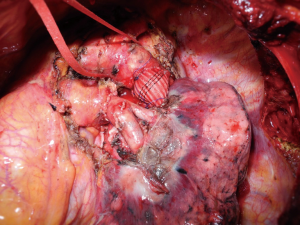

侵犯胸主动脉的肺癌整体切除是另一个有争议的话题[13]。这是一个非常精细且复杂的过程,许多技术已被报道过[14]。虽然难以实现,但根治性切除术可以获得良好的肿瘤学结果,并具有合理的发病率和死亡率。重建技术的选择基于受侵部位(主动脉弓或降主动脉)、管周受累程度和管壁受累深度。如果主动脉浸润局部局限于外膜,且主动脉壁内的切除平面可以容易构建,则可以在包围浸润区域下方和上方的主动脉进行外膜下切除,方便最终紧急夹闭。当主动脉中层有确认或可疑的侵犯,且肿瘤侵犯大于主动脉周长的30%,不同的方法可以选用:直接夹闭主动脉进行主动脉壁切除和重建,特别是在侵犯血管定位在降主动脉水平的情况下[15];当主动脉弓受侵犯时,可以在股静脉和股动脉之间进行部分体外循环,或者从升主动脉到降主动脉行临时旁路移植术,这样有可能重建受浸润的锁骨下动脉或颈动脉[16]。另外,最近,术前或术中主动脉内移植物的放置和主动脉/主动脉弓交叉夹闭技术切除成功地应用于安全的主动脉壁切除,避免了使用体外循环[17,18](图1)。